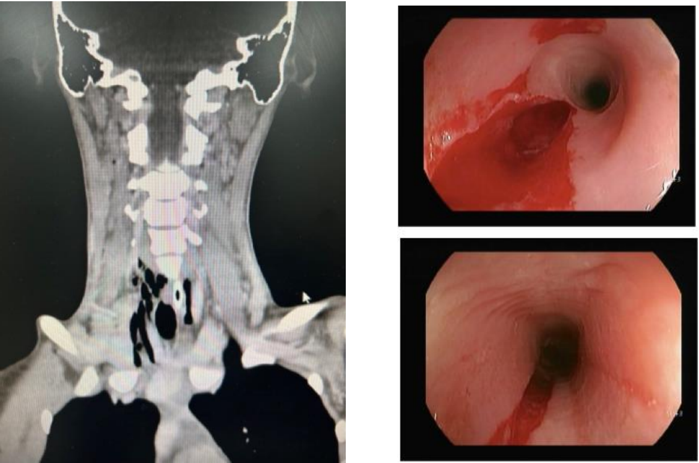

Endoscopia laudava esôfago com mucosa conservada até 20cm da ADS com laceração profunda onde encontra-se corpo estranho impactado. Retirado com auxílio de Roth Net sem intercorrências. Realizada também tomografia computadorizada de pescoço. Vide imagens abaixo.